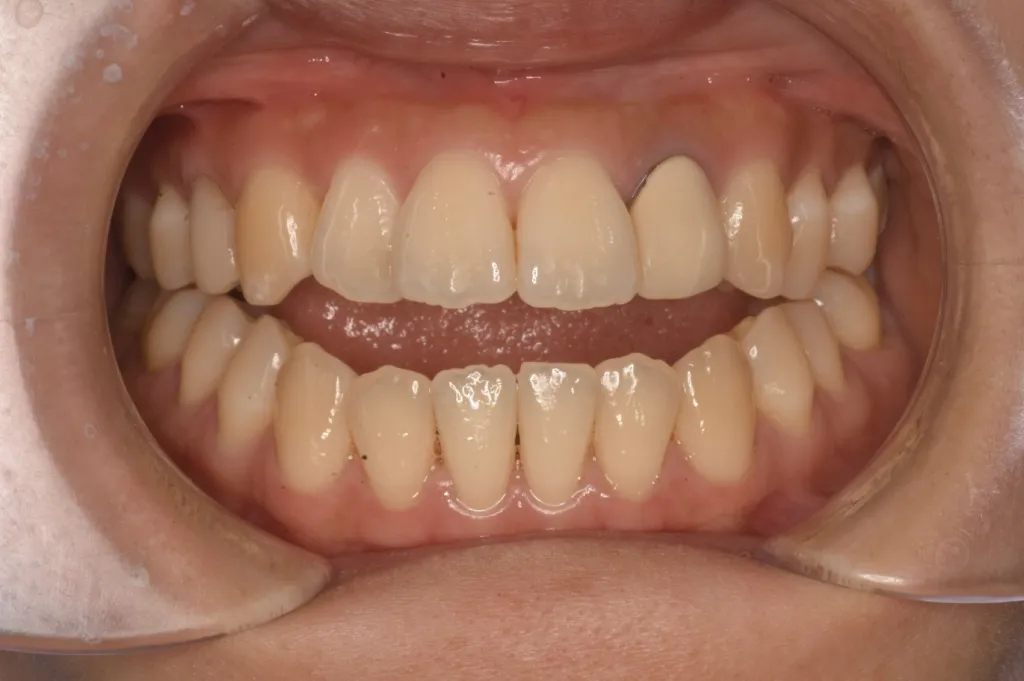

• 治療前 開咬(オープンバイト)と呼ばれる状態

治療前 開咬(オープンバイト)と呼ばれる状態

患者さんのお悩み、希望 前歯がまったく噛んでいないため、滑舌が悪く、前歯でものが噛み切れないことに悩まれていました。何件か矯正相談に行ったが、どこでも「顎を切る手術をしないと治らない」と言われ諦めかけていました。手術は回避したいが、噛み合わせを治したいという強いご希望がありご来院されました。

治療方法 マウスピース矯正(インプラントアンカー併用)。 開咬に加え受け口傾向であったため、ワイヤー矯正では手術が必要な歯並びでしたが、マウスピース矯正で奥歯を圧下し、インプラントアンカーを併用して下顎の奥歯を後方に移動させ、開咬と受け口を改善しました。

治療期間 1年10ヶ月

マウスピース矯正とインプラントアンカーを併用することで手術なしで開咬の改善を行いました。